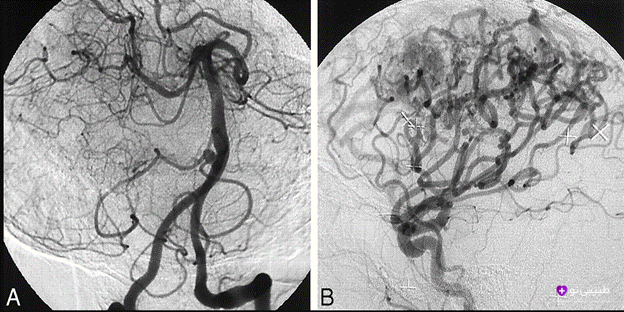

آنژیوگرافی مغز روشی دقیق برای مشاهده رگ‌های خونی مغز و گردن با استفاده از اشعه ایکس و تزریق ماده رنگی است. این روش معمولاً زمانی انجام می‌شود که سایر روش‌ها پاسخگو نباشند و نیاز به بررسی دقیق‌تر باشد. آنژیوگرافی توسط متخصص رادیولوژیست مرتبط با این حوزه انجام شده و به انتخاب بهترین راه درمان کمک می‌کند.

آنژیوگرافی مغزی اطلاعات سه‌بعدی با وضوح بالا از ساختار و مسیر رگهای خونی مغز ارائه می‌دهد و تحلیل جریان خون را به صورت زنده ممکن می‌سازد. اگرچه عوارض عصبی دائمی نادرند (حدود ۱٪)، اما با افزایش سن (بالای ۵۵ سال) احتمال آن بیشتر می‌شود. شایع‌ترین مشکلات مرتبط عبارتند از سکته‌ امبولیک، هماتوم ناحیه کشاله ران و آسیب کلیوی ناشی از ماده حاجب.

آنژیوگرافی مغز